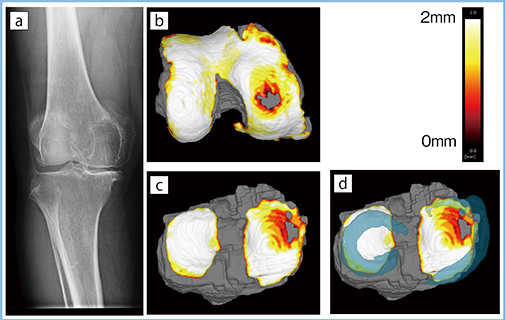

レントゲンで大腿骨と脛骨の隙間として描出される関節裂隙は,大腿軟骨,半月板,脛骨軟骨の3層構造となっている。富士フイルムと共同開発した膝MRIの全自動3D画像解析システムでは,膝MRIの画像データを取り込むと,骨,軟骨,半月板が自動抽出され,三次元画像が表示される。解析結果として得られる軟骨厚みマップでは,軟骨の厚さが2mm以上では白,薄くなるにつれて黄,赤で示され,半月板を重ねて表示できる。KL grade3の例(図1)では,レントゲン像(a)で内側裂隙の狭小化と大きな骨棘を認め,大腿軟骨の厚みマップ(b)では内顆中央に軟骨欠損を,脛骨軟骨の厚みマップ(c)では内側に軟骨欠損を認める。大腿軟骨と脛骨軟骨の欠損部分が接すると考えると,大腿骨に対して脛骨が外側に偏位していると予測できる。さらに半月板を重ねると,内側後方が断裂し,内側半月板が内方に逸脱していることがわかる(d)。このように,3D画像ではレントゲンではわからない軟骨や半月板の病態を明らかにすることができる。

図1 KL grade3の例の解析結果